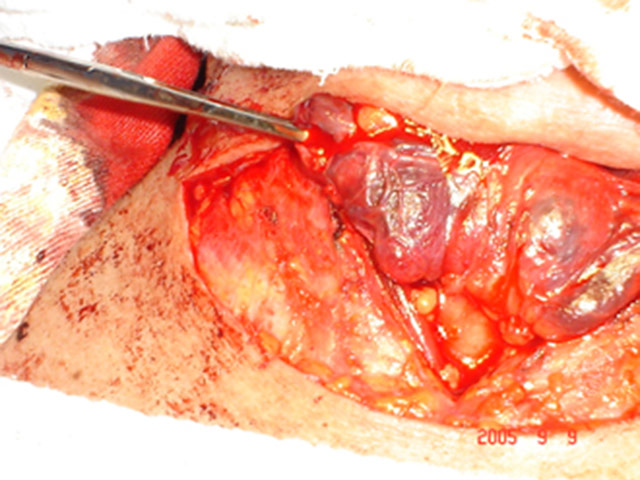

Tumor de Tireóide II

Carcinoma Papilífero Bilateral

Vemos a tireóide dissecada.

Seta mostrando o tumor maior no lobo.

esquerdo. Lobo direito com microcarcinoma.

Peça cirúrgica.